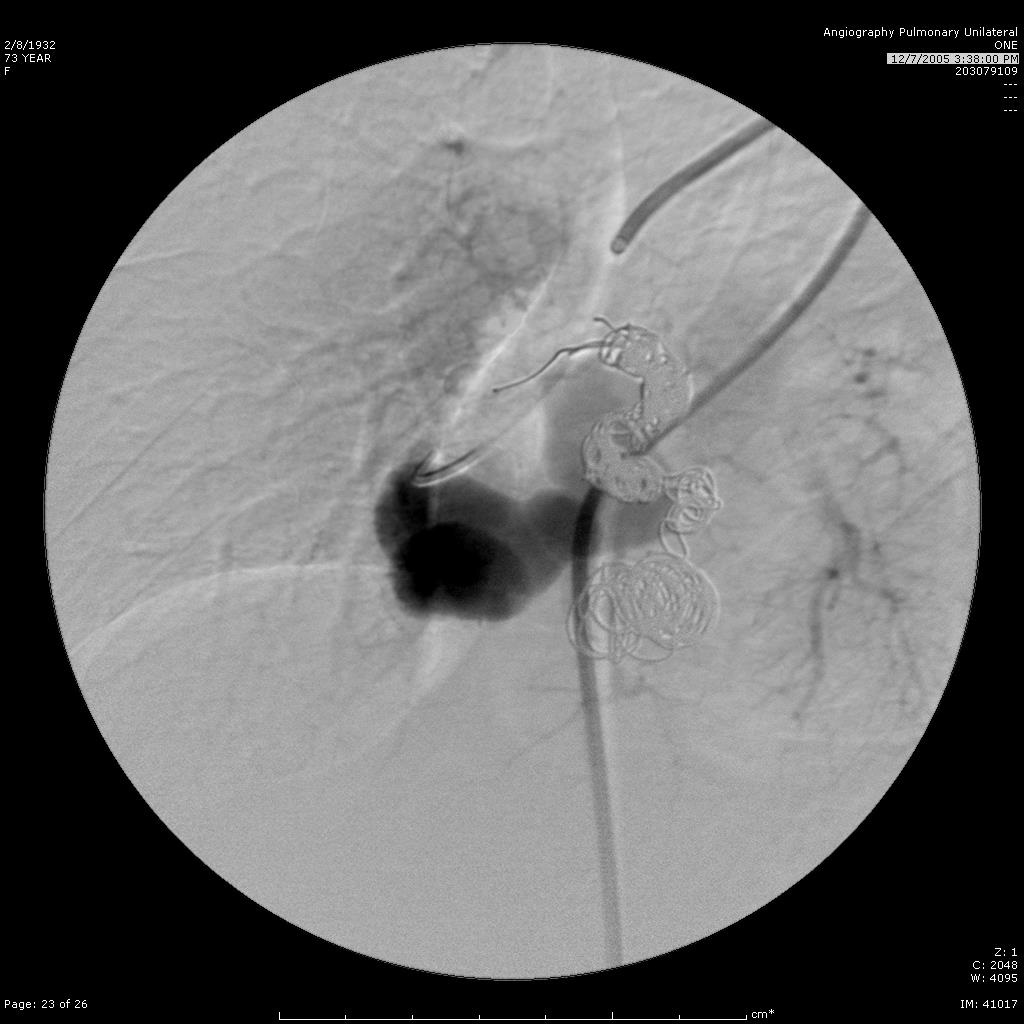

选择性进入滋养动脉 |

栓塞后弹簧栓子逸出至右肺静脉 |

栓塞后弹簧栓子逸出至右肺静脉 |